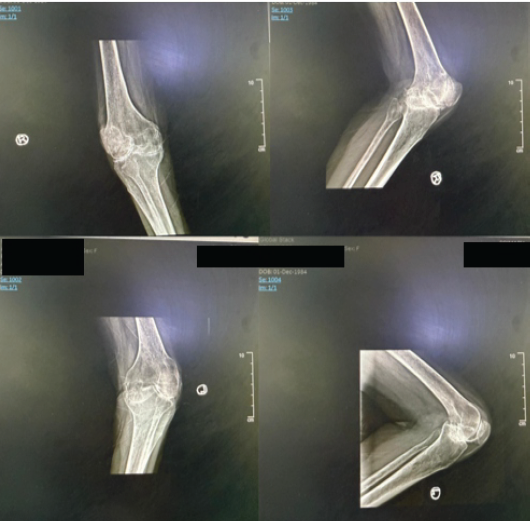

Radiographs of the hips and knees showed significant joint damage, evident through reduced joint space and deformities. The X-rays for the right and left knee revealed total joint space loss and periarticular osteopenia (Fig. 2).

Figure 2: Pre-operative anteroposterior and lateral X-ray of the right knee and left knee (June 25, 2024).